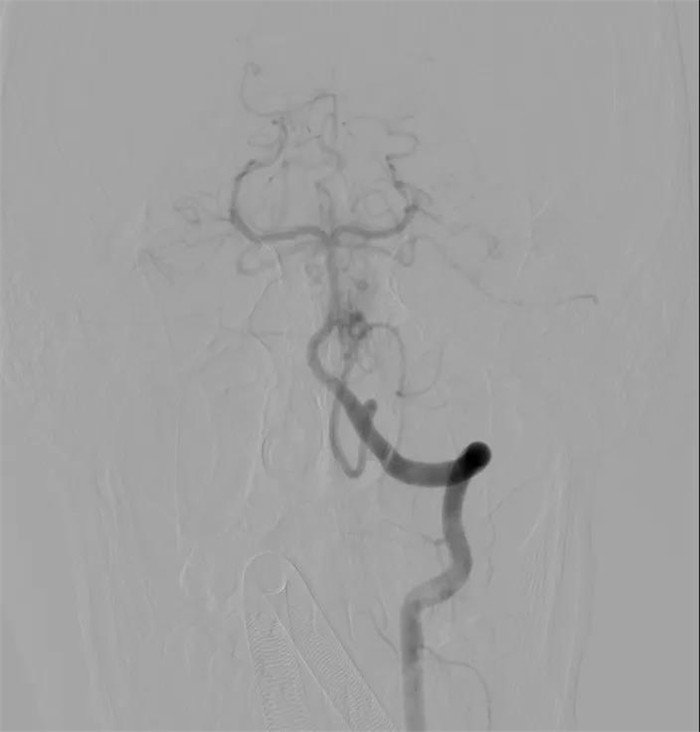

“复合手术室可以对手术患者进行血管造影检查,根据造影检查结果进行手术,并随时可以造影查看手术效果,不必再像以往那样先做造影,再进手术室手术,然后再推出手术室做造影。” 陈晓霖介绍,小豪的全脑血管数字减影造影显示,他的出血病灶是位于小脑蚓部的脑动静脉畸形,而且右侧小脑上动脉和双侧小脑后下动脉都参与了动静脉畸形的供血,动脉极其迂曲,不论是栓塞前的微导管超选还是栓塞后的微导管撤出都存在一定难度。

根据造影结果,医生们选择对右侧小脑上动脉和左侧小脑后下动脉进行栓塞以降低术中出血风险。由于动脉迂曲、活动度极大,微导丝和微导管的每一寸进退都冒着刺破动脉的风险,足足用了一个小时,两支目标动脉中病灶的供血分支和一部分病灶被成功栓塞,正常血管分支被完整保留。

“我建议尝试通过最后这支供血动脉争取完全栓塞,开颅只做血肿清除,尽量减少对脑干的影像。”陈晓霖说,大家随后对最后一支供血动脉发起“进攻”。通过不断调整微导丝的形态,将微导管超选到尽可能靠近畸形巢的位置,王明泽向微导管内推入栓塞剂。随着一团栓塞剂慢慢出现在引流静脉与病灶交界的位置,畸形完全被栓塞,经过造影复查,原本“一团乱麻”的病灶区域十分干净,只有几团栓塞剂的痕迹若隐若现,小脑的各个分支动脉都被完好保留!